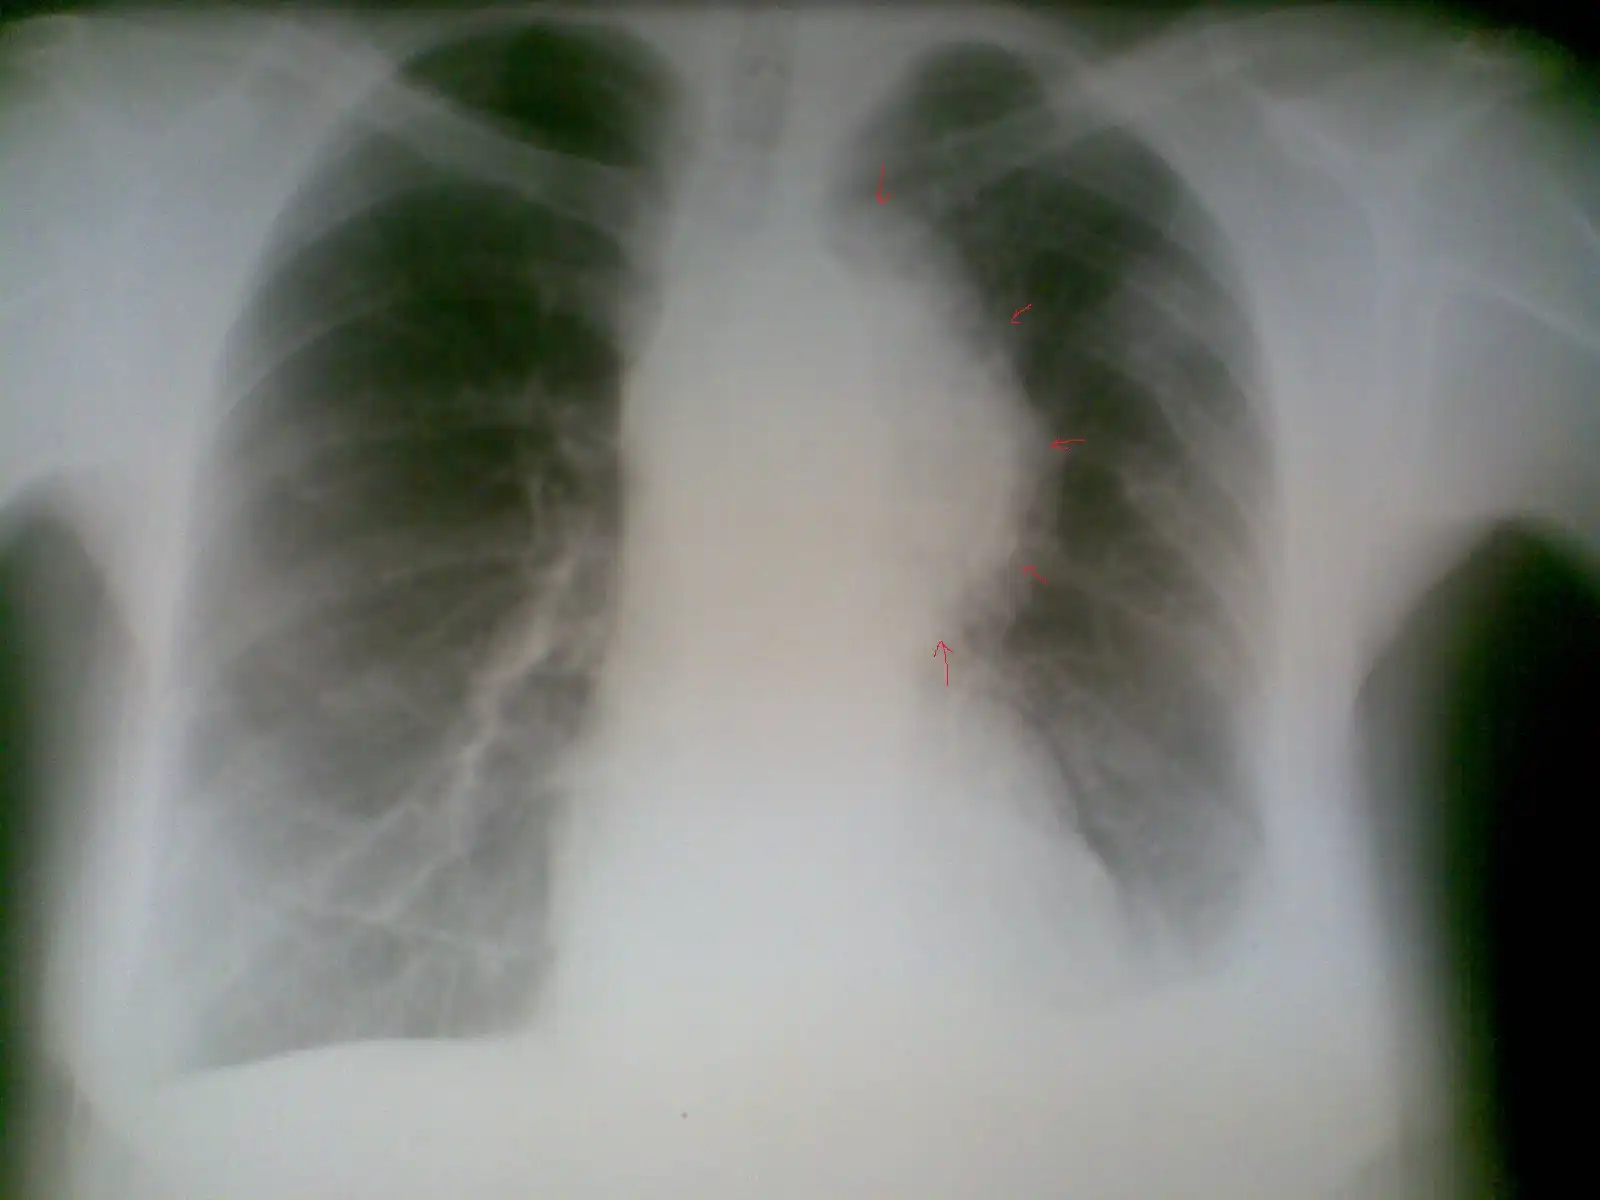

Пациент № 1: